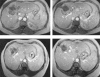

Established ablative therapies for the treatment of primary and secondary liver tumours, including percutaneous ethanol injection, cryotherapy, and radiofrequency ablation, are discussed. Newer techniques such as magnetic resonance imaging guided laser interstitial thermal therapy of liver tumours has produced a median survival rate of 40.8 months after treatment. The merits of this newly emerging technique are discussed, together with future developments, such as focused ultrasound therapy, which holds the promise of non-invasive thermoablation treatment on an outpatient basis.